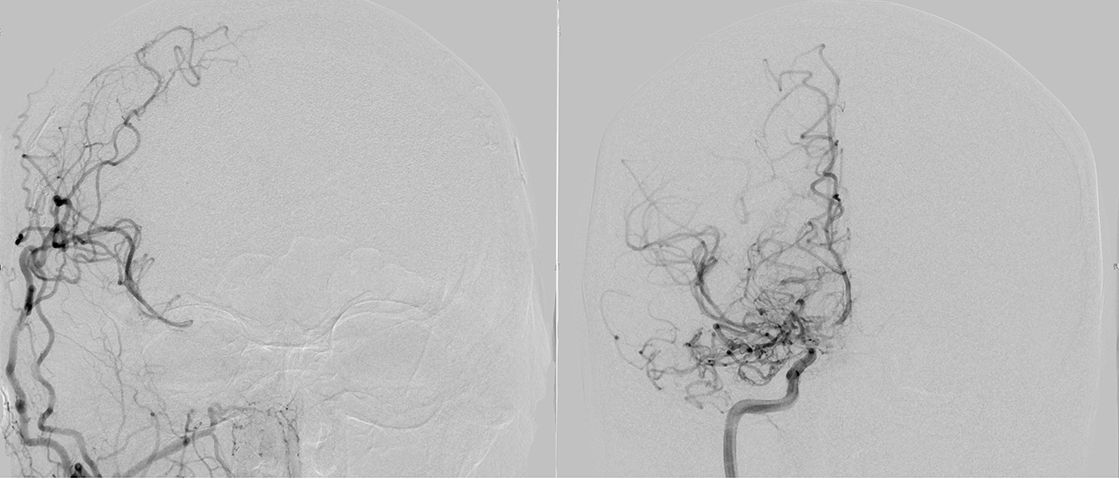

Angiographie zur Darstellung der zusätzlichen Blutversorgung des Gehirns

1 Jahr postoperativ: Angiographie zur Darstellung der zusätzlichen Blutversorgung des Gehirns über den Bypass (linke Seite) in Ergänzung zu der unzureichenden Versorgung über die innere Halsschlagader (rechte Seite).

Je nach Bedarf wächst das Spendergefäß dann im Verlauf deutlich und kann so große Teile des Gehirns mitversorgen. Generell ist eine solche direkte Verbindung stets die Therapie der Wahl, da so direkt mehr Blut ins Gehirn kommt. Im seltenen Fall, dass eine direkte Verbindung auf Grund ungeeigneter Empfänger- oder Spendergefäße nicht möglich ist, kann auch ein indirekter Bypass gelegt werden. Hierbei legt man gut durchblutete Gewebeschichten des Kopfes auf die Hirnoberfläche und wartet auf das Einsprießen von Gefäßen, die dann dem Hirn mittelfristig mehr Blut zur Verfügung stellen sollten.